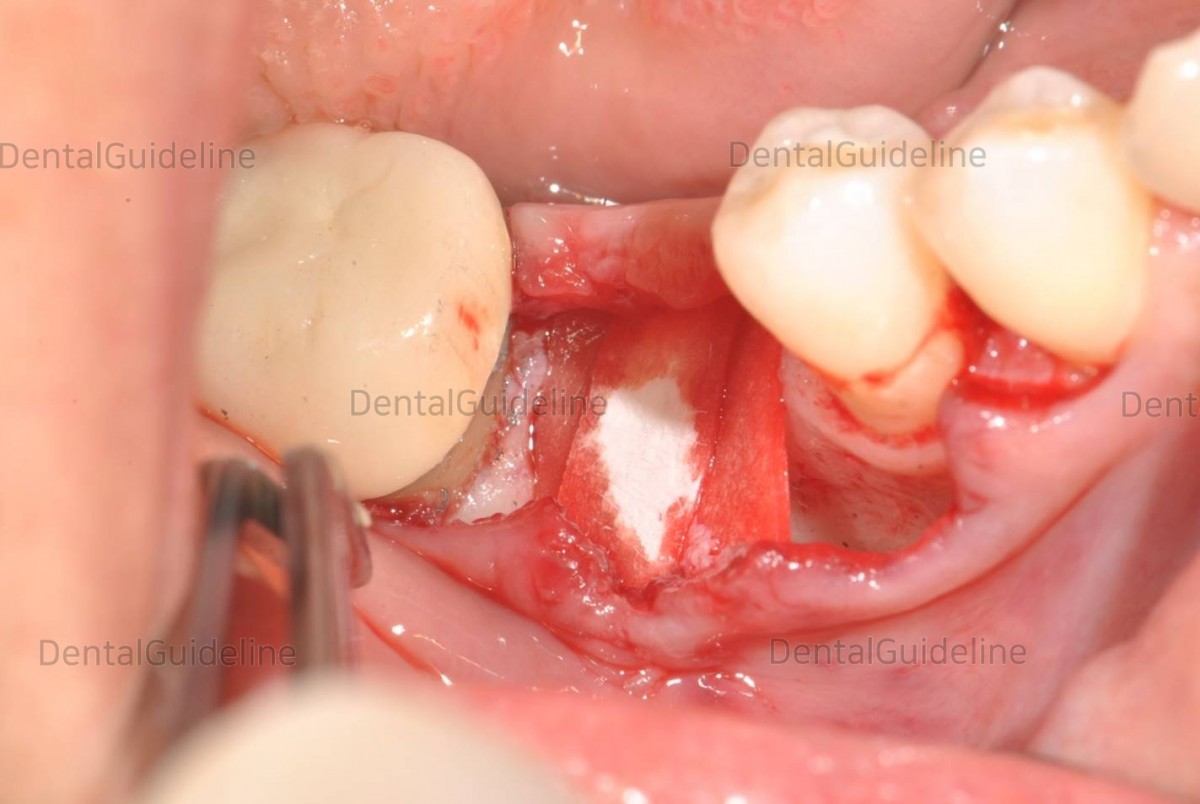

GBR (FDBA, cortical)

BONE-PACKER

Fully grafted site'

Collagen membrane